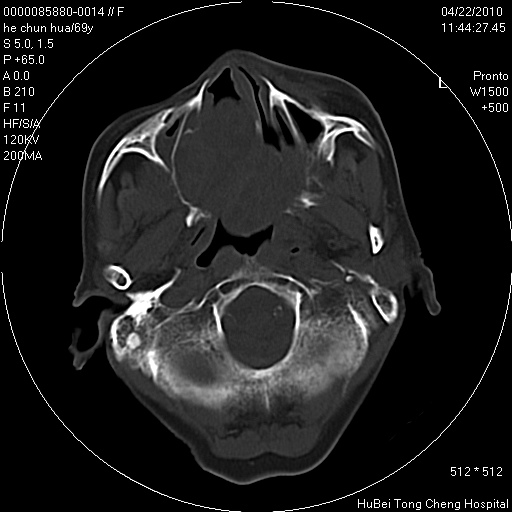

标题: CT25937:女,69Y

硬腭部包块十余年,渐进性增大。